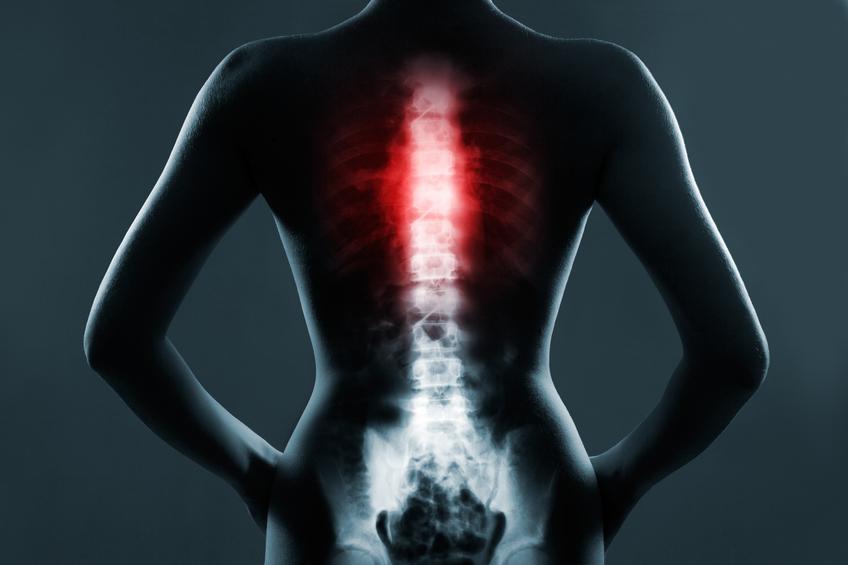

El cuerpo humano está dividido en tres partes importantes: la cabeza, el tronco y las extremidades. Concretamente, el tronco está dividido a su vez en tres partes conocidas como tórax, abdomen y pelvis. El tórax o caja torácica es la parte superior del tronco que empieza desde la base del cuello hasta el diafragma, el músculo que separa el tórax del abdomen. Además, tiene la forma de un cono con la base más grande que la parte superior y puede ensancharse para ayudar en la función de los pulmones.

En el tórax se encuentran varios órganos vitales como el corazón, los pulmones, parte de la tráquea y del esófago, así como arterias y venas, por ejemplo, la arteria aorta y la vena cava. Por lo tanto, los huesos de la caja torácica protegen a los órganos vitales de posibles traumatismos, siendo esta una de sus funciones más importantes.

Cuáles son los huesos del tórax - ¿Qué es el tórax?